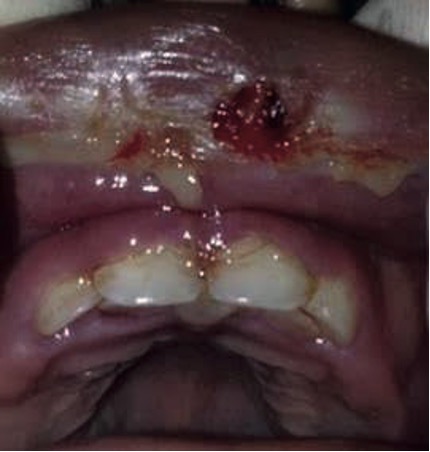

Evolución clínica: Reevaluación clínica a los 15 días post tratamiento (Figura 3a,3b,3c) se observa disminución en número, tamaño y severidad de las lesiones, ausencia de cuadros febriles con aumento en apetito.

Figura 3. Reevaluación clínica.